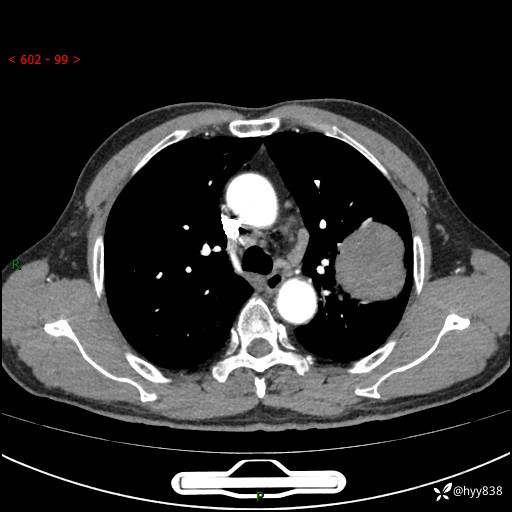

68岁/男,发现左下肺占位5天。如此大的肿块,患者竟然没有症状---结果公布~

【患者信息】:68岁/男

【主诉】:检查发现左下肺占位5天。

【现病史及既往史】:患者于4天前外院行“经尿道钬激光碎石术”,住院期间胸部CT检查发现左下肺肿块,患者平素无明显咳嗽咳痰,无心慌、胸闷、胸痛、呼吸困难、低热、盗汗,无头痛、头晕,无腹痛、腹胀等不适,现患者为求进一步治疗,遂来我院就诊,以“左下肺肿块”收入我科。 患者自起病以来,精神可,睡眠可,饮食可,大小便正常,体重无明显改变。

【检查】:胸部CT增强扫描